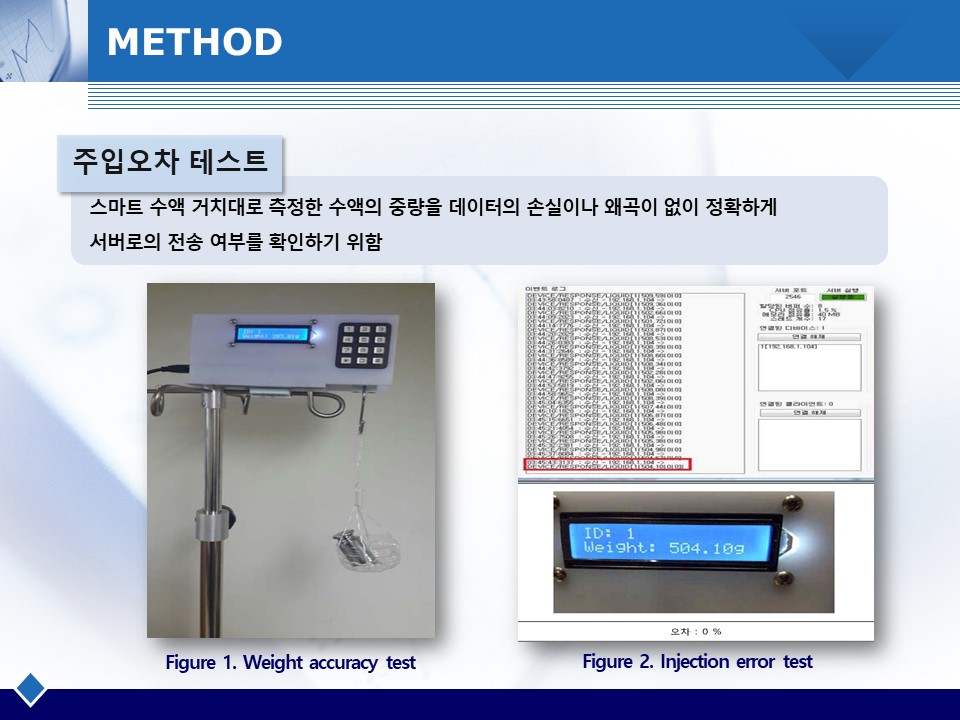

수액투여 시 의료사고를 방지하고 정확한 양의 수액을 투여하기 위한 자동화 및 모니터링 시스템을 개발함. 스마트 수액 거치대를 통해 실시간 수액의 중량변화를 모니터링하고, 오토-레귤레이터가 자동으로 유량을 조절함. 수액 거치대와 오토-레귤레이터를 설계 및 제작하고 주입오차 테스트를 통해 정밀도를 측정함.